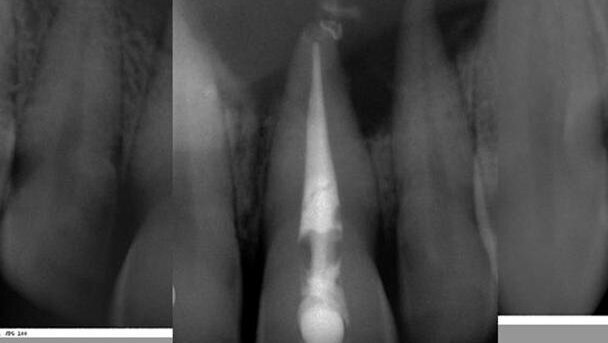

1. During the first visit, the previous root-canal filling (gutta-percha with a plastic carrier) was removed (Fig. 5). There was a lot of gutta-percha in the pulpal camera. This and remains of necrotic pulpal tissue could have been the cause of the brown staining of the tooth. Once the buccal encapsulated tissue had been removed (Fig. 6), both the tooth and buccal abscess were drained of copious exudate. A Ca(OH)2 paste (UltraCal XS, Ultradent) was placed in the root canal as interim medication (Fig. 7).

4. Two months later, healing appeared to be underway (Fig. 11a) and the canal was dry. The root-canal filling was performed with gutta-percha and AH Plus (DENTSPLY DeTrey) and composite were placed to seal the access (Fig. 11b).